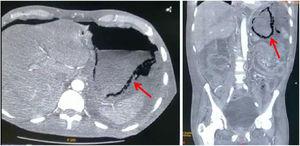

Un paciente varón de 57 años, diabético, hipertenso y con tabaquismo positivo suspendido ingresa por presentar cambios de coloración en los ortejos del pie derecho, llenado capilar retardado e hipotermia local y zonas de necrosis sin datos de infección. Se integra un diagnóstico de pie diabético, grado 4 de la clasificación PEDIS y enfermedad renal crónica. Durante su hospitalización presenta descontrol metabólico y desarrolla acidosis, se inicia diálisis peritoneal, con colocación percutánea de catéter Tenckhoff, el cual presenta salida de líquido turbio, por lo que se da manejo antibiótico con ceftriaxona y clindamicina. Posteriormente presenta dolor abdominal, signo de rebote positivo y peristalsis disminuida, agregándose hipotensión. Ante la sospecha de infección intestinal se cambia el esquema por meropenem, profilaxis fúngica y metronidazol. Se pide una tomografía computarizada en la que se evidencia gastritis enfisematosa y aire libre en la cavidad (fig. 1), también se solicitan estudios de laboratorio (tabla 1) y se opta por realizar una laparotomía exploratoria. Durante el evento se drena líquido purulento de la cavidad abdominal, se aprecian múltiples adherencias en el cardias que son eliminadas. También se observaron áreas de necrosis desde el píloro hasta el esófago, se colocó una sonda orogástrica y se aspiró el contenido gástrico, lo que mejoró parcialmente la perfusión, y se continuó el lavado usando soluciones tibias. Ante el estado crítico del paciente, que persistía con hipotensión e hipoglucemia, se decidió terminar el acto quirúrgico por máximo beneficio, sin embargo continuó con estado de choque y descontrol metabólico hasta que se otorgó el alta voluntaria por petición familiar.

El hallazgo de gastritis enfisematosa fue contundente para llegar al diagnóstico de isquemia gástrica ocasionada por la trombosis del tronco celíaco en nuestro paciente. Este era diabético e hipertenso, aunado al proceso isquémico en el pie derecho, además comienza con ERC grado 5, enfermedad que genera un estado de hipercoagulabilidad. En la necrosis intestinal, hay factores que brindan información sobre la probabilidad de estar ante el diagnóstico correcto y el manejo a seguir, entre ellos se encuentran la hipertensión arterial, la dislipidemia, antecedente de isquemia al miocardio o en las extremidades, fallo orgánica, leucocitosis, lactato sérico elevado, alteraciones en el grosor de la pared intestinal y la dilatación de las asas intestinales. Dichos factores aumentan la probabilidad de muerte, llegando hasta el 40% con la presencia de 3 de ellos2,4,7. Drucker et al. describen que la neumatosis se puede asociar a isquemia, y dentro las presentaciones tomográficas identificables que la acompañan está el encontrar aire en la vena porta8, por lo que sugieren una búsqueda intencionada de este dato. Desafortunadamente nuestro paciente no lo presentaba2,4 y la neumatosis tenía una distribución lineal que, al presentarse en el estómago, no fue de mucha ayuda al determinar el manejo a seguir9. El tratamiento puede ser quirúrgico o conservador, con la corrección de cualquier desequilibrio hidroelectrolítico. Drucker et al. presentan un caso en el que se prefirió hidratar al paciente y colocar una sonda nasogástrica10, aunque también se puede optar por la intervención quirúrgica. En el estudio de Spektor et al. se encontró que la neumatosis gástrica más la elevación de los niveles séricos de creatinina y ácido láctico se asoció con una mayor mortalidad, por lo que se deben tomar en cuenta en la decisión del manejo3,9. Sin embargo es necesario evaluar el estado de cada paciente y recordar que la extensión de la isquemia, los factores de riesgo y los hallazgos tomográficos desempeñan un rol vital en la decisión de la terapéutica a seguir2,3,9.